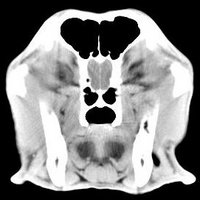

imágenes de TC en el perro | ||||||||||

ejemplo de imágenes de TC en el perro. Nótese la celulitis en la región parotídea izquierda | ||||||||||